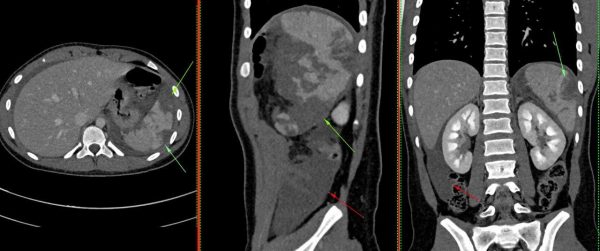

- КТ: створює детальні зображення кісток та м’яких тканин у вигляді “зрізів”. Дозволяє виявити навіть найменші зміни.

Комп’ютерна томографія: Надає детальні зображення внутрішніх органів та тканин, допомагає виявити пухлини, запалення та травми.

- Комп’ютерна томографія: Siemens SOMATOM X.cite (128 зрізів, мах. 364 реконструйовані зрізи)